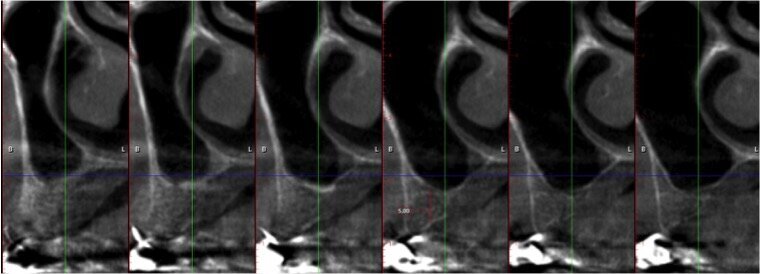

La paziente, di sesso femminile e con anamnesi medica negativa, si presenta in visita lamentando mobilità della protesi fissa presente nel II quadrante. Dopo l’esame obiettivo e strumentale gli elementi 23 e 27 (pilastri di ponte) vengono reputati non mantenibili e si programma l’estrazione degli stessi. Contestualmente all’estrazione si pianifica, con lo studio della CTCB pre-operatoria, l’inserimento di 3 impianti e la futura riabilitazione implanto-protesica fissa con pilastri di ponte 23-24-25. L’altezza di cresta residua è circa di 4/5 mm in altezza per le tre sedi (Figg. 1-4). La paziente riceve una profilassi antibiotica di tipo Short-term (Amoxicillina + Acido Clavulanico 2 g 1 ora prima dell’intervento) e fa uno sciacquo di 1 minuto con CHX 0,2% prima della chirurgia.

Quando le frese Densah successive avanzano nell’osteotomia, l’osso viene spinto (o densificato) verso l’estremità apicale e comincia a sollevare gradualmente la membrana di Scheneider con l’osso autologo compattato. Utilizzare sempre le frese con movimento di “pompaggio” e abbondante irrigazione, al fine di non surriscaldare l’osso. Per raggiungere una maggiore profondità verticale e il sollevamento graduale della membrana senza perforazioni si consigliano incrementi di 0,5 1,0 mm per fresa, fino ad ottenere la lunghezza e il diametro finale desiderato. Si ricorda che le frese in successione possono raggiungere un sollevamento della membrana di massimo 3 mm. Vista la scarsa qualità e quantità ossea residua del caso in questione, pur usando le frese Densah in modalità di osseodensificazione non si riesce a mantenere una integrità ossea della porzione apicale dei siti osteotomici (Fig. 5). Nei casi di incrementi superiori a 3 mm si può collocare all’interno dell’osteotomia del materiale da innesto, utilizzando l’ultima fresa con velocità di 150-200 giri/min senza irrigazione e in senso antiorario, per compattarlo all’interno dell’osteotomia. In questo caso si posizionano delle membrane di PRF all’interno dei siti osteotomici, così che la membrana di Schneider venga sollevata idrostaticamente con leggere pressioni del PRF (Fig. 6). Finita la fase di preparazione dei siti osteotomici si può procedere all’inserimento implantare a 20 giri/min e 50 Ncm di coppia (Fig. 7). Si esegue a questo punto un innesto di osso eterologo tipo “L-PRF-block”7 per incrementare il volume della zona vestibolare (Fig. 8). Sull’innesto vengono posizionate delle membrane di PRF assottigliate (Fig. 9) e una ulteriore membrana riassorbibile viene posizionata sopra il PRF per assicurare l’immobilità del tutto (Fig. 10). Si procede con l’esecuzione di scarichi di rilascio periostali, per avere un lembo privo di tensioni muscolari (Fig. 11). Infine, viene eseguita una sutura con filo 5 zeri riassorbibile monofilamento (Fig. 12). Nell’immediato post-operatorio viene eseguita alla paziente una CTCB di controllo. Come si può notare dalle sezioni della stessa, la membrana sinusale non risulta perforata, ed è sollevata sugli impianti (Figg 13, 14). Notare la neoformazione ossea apicale agli impianti a 5 mesi dall’intervento (Fig. 15).

Fig. 2 - Cross section di zona 23.

Fig. 3- Cross section di zona 24.

Fig. 4 - Cross section di zona 25.

Fig. 14 - Sezione cross section post-operatia zona 24.